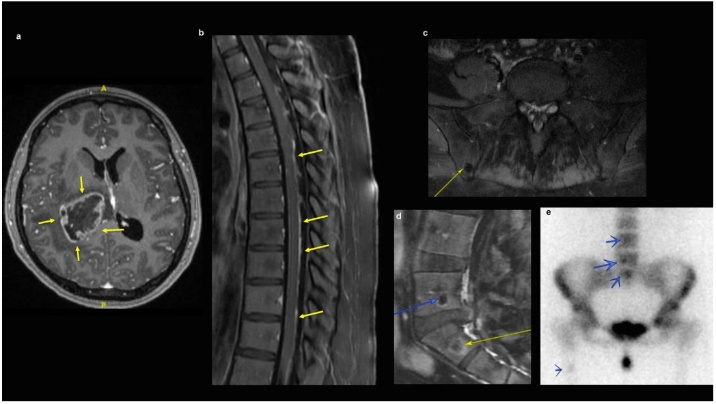

20岁女性,头痛伴呕吐。颅脑MRI显示右侧丘脑强化病灶,病灶中心坏死(图2a)。患者行肿瘤次全切除,病理学提示DMG伴H3K27M突变型pHGG。新一代测序(NGS)显示,H3F3A(p.K28M)突变,伴TP53突变(表1)。患者接受60Gy的局部放疗,以及替莫唑胺同步化疗6周。此后,继续替莫唑胺周期性化疗。化疗3个周期后,脑和脊髓MRI显示脑内病灶增大,并出现新发颅内和脊髓LMD,以及新发溶骨性病变(图2b、c、d)。骨扫描示脊柱和右侧股骨转移性病变(图2e)。

图2. H3K27M突变型弥漫性中线胶质瘤伴脑外转移的影像学特征。17岁女性,头痛伴复视2周。颅脑MRI显示累及左侧海马延伸至左侧中脑后部的强化病变,伴颅内广泛LMD(图3a)。脊柱MRI提示弥散性病变(图3b)。脑组织活检确诊DMG伴H3K27M突变pHGG。脑肿瘤NSG结果为H3F3A(p.K28M)和TP53突变(表1)。放疗后7周,患者出现呼吸短促,胸部CT发现大量胸腔积液(图3c)。胸部、腹部和骨盆CT示纵隔和肺门淋巴结肿大,肺和胸膜多灶性结节,多发低强化肝脏病变,大网膜脂肪束与转移性病变一致(图3c、d)。胸腔积液检查为88%的恶性细胞,腹壁软组织病变活检(图3d)和皮肤活检证实为转移性H3K27M突变型pHGG。